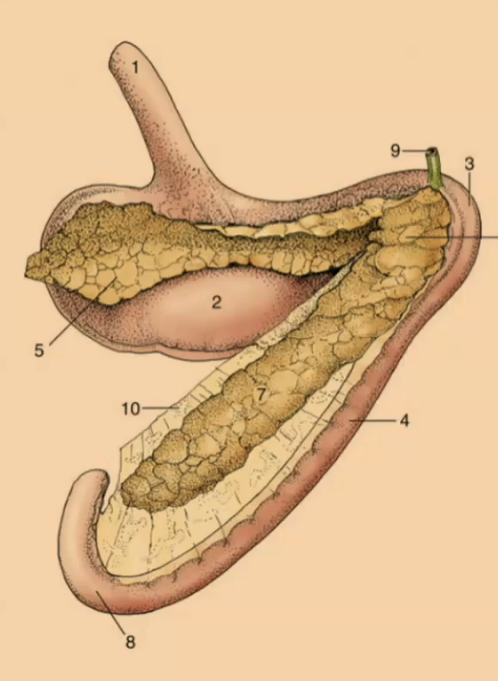

Pancreas

What is the function of the pancreas?

#6? #7? #5?

6: Body 7: Right lobe 5: Left lobe

The left lobe of the pancreas is close to what?

the stomach

#9

Bile duct

In what species are there separate openings in the duodenum for the bile and pancreatic duct?

canine, feline, cattle

In what species is there a common opening in the duodenum for the bile and pancreatic duct?

equine, sheep, goats